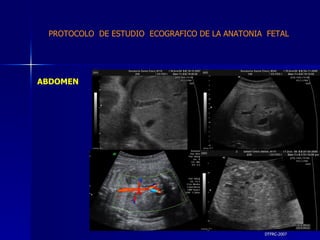

DTFRC-2007 ABDOMEN PARED ABDOMINAL DIAFRAGMA PROTOCOLO  DE ESTUDIO  ECOGRAFICO DE LA ANATONIA  FETAL

DTFRC-2007 ABDOMEN PROTOCOLO  DE ESTUDIO  ECOGRAFICO DE LA ANATONIA  FETAL